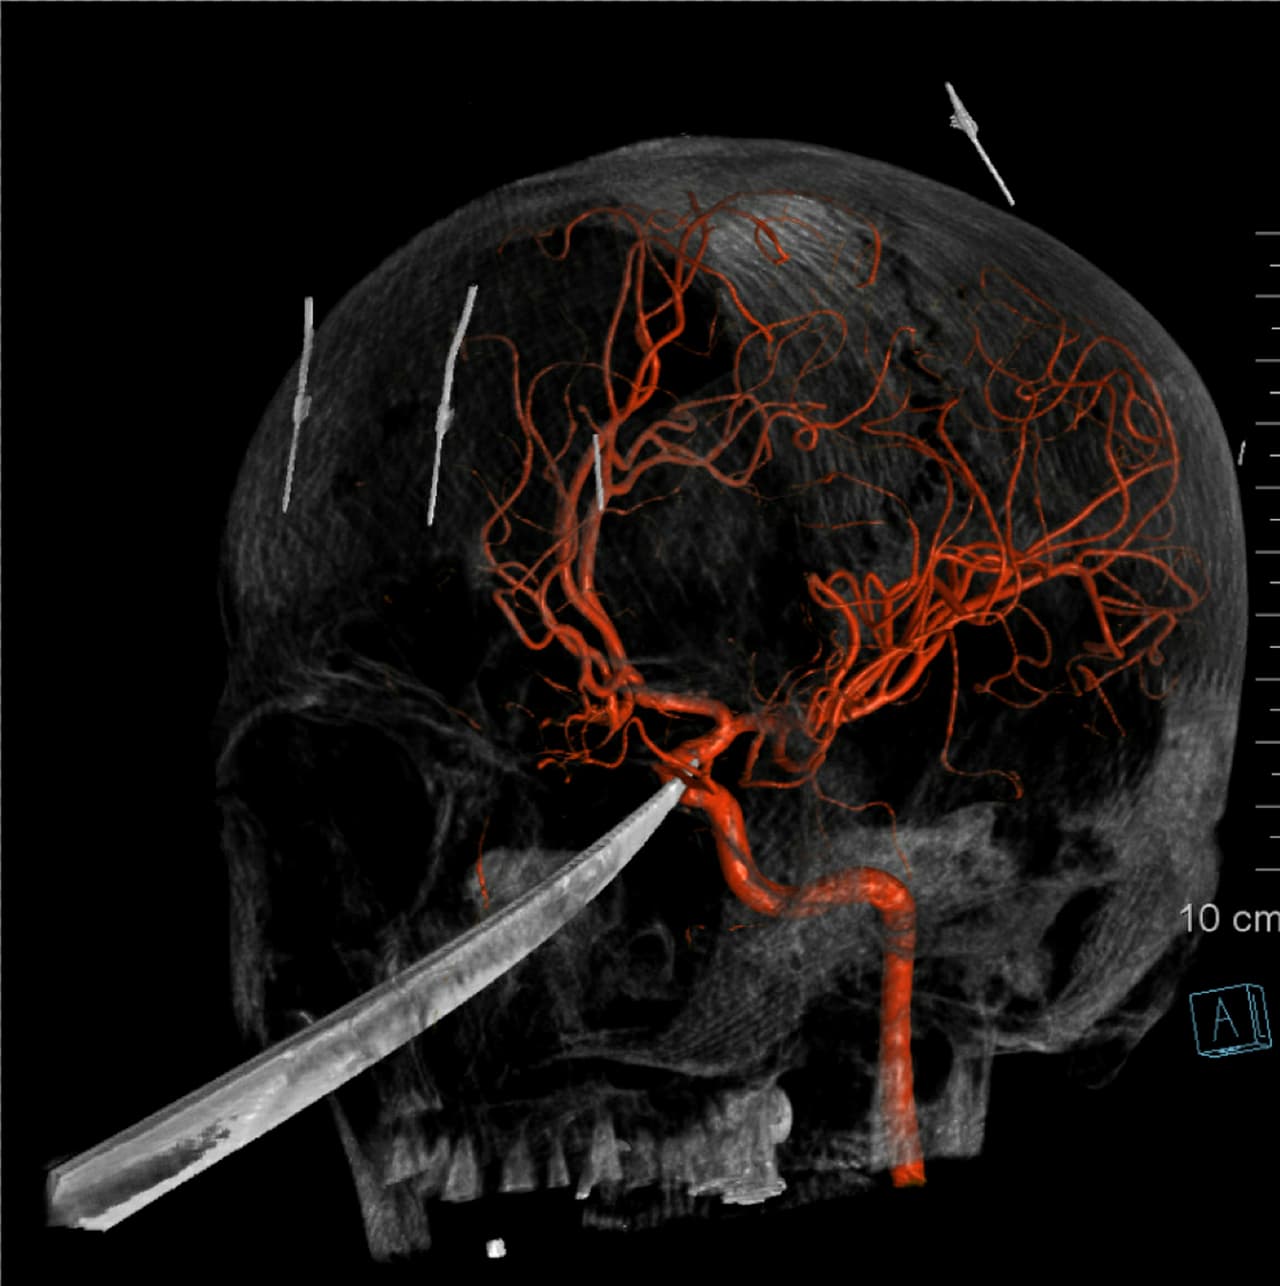

Una imagen de rayos X mostraba la profundidad de la herida de en la cara de Eli Gregg: la hoja del cuchillo estaba clavada en su cráneo y alcanzaba hasta justo debajo de su cerebro; la punta del arma presionaba su arteria carótida, que abastece de sangre al cerebro.

Los médicos se prepararon para una posible hemorragia cerebral, pero la operación se realizó sin problemas y la arteria permaneció intacta. Ebersole y sus colegas utilizaron catéteres, globos diminutos y otras herramientas para extraer el arma cuidadosamente.